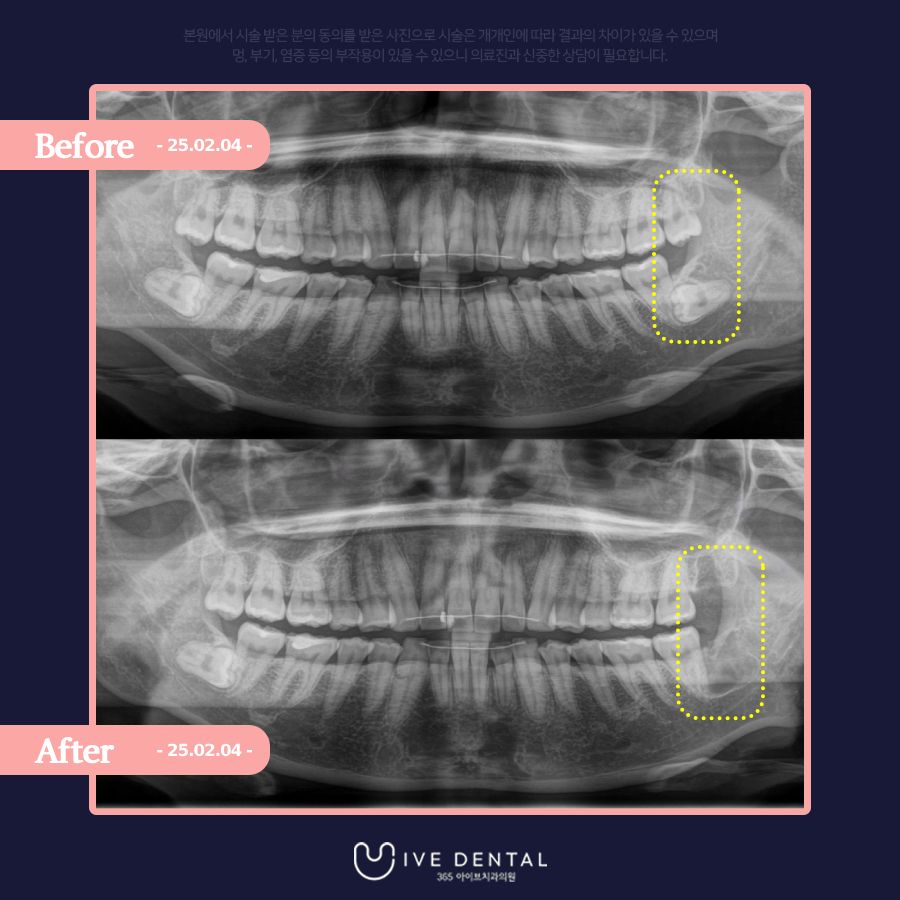

돌출 사랑니와 매복사랑니가 있는 30대 환자분

군산에 사시는 30대 여성 환자분이신데요!

​양쪽 상악에 돌출 사랑니와 하악에 매복 사랑니가 보입니다.

저희 아이브치과에서는 양쪽 사랑니 4개 모두 하루에 발치 진행이 가능하지만, 환자분께서는 왼쪽 사랑니부터 발치를 원하셨습니다.

​마취 후 바로 전주사랑니발치를 진행하였고요

환자분을 골치 아프게 하던 사랑니가 깔끔히 제거된 것이 보이시나요?

매복사랑니와 돌출 사랑니 발치에 총 걸린 시간은 5분 내외입니다.